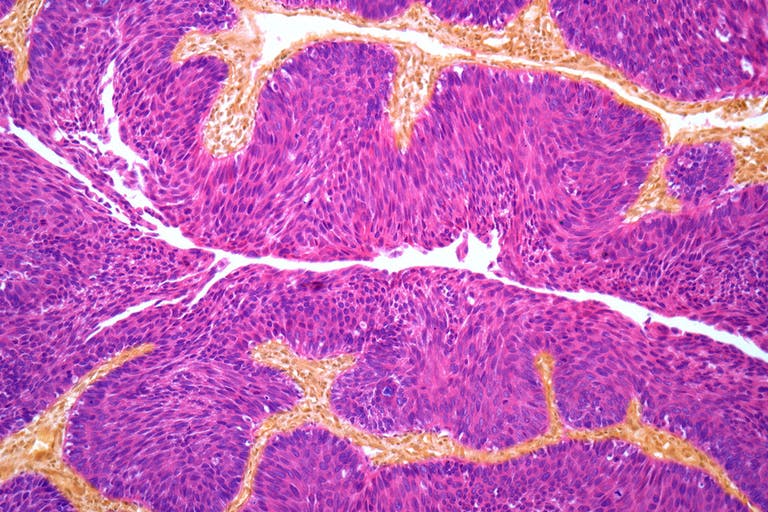

Oltre 300 mila italiani, un sesto circa donne, vivono con un tumore della vescica, che rappresenta il 3% di tutti i tumori ed è il secondo tumore urologico nell’uomo dopo quello della prostata. Una malattia che ha registrato un aumento dell’8 per cento solo nell’ultimo anno e che è fondamentale individuare precocemente, e soprattutto in modo preciso, con un’analisi genomica che ne definisca il profilo molecolare.